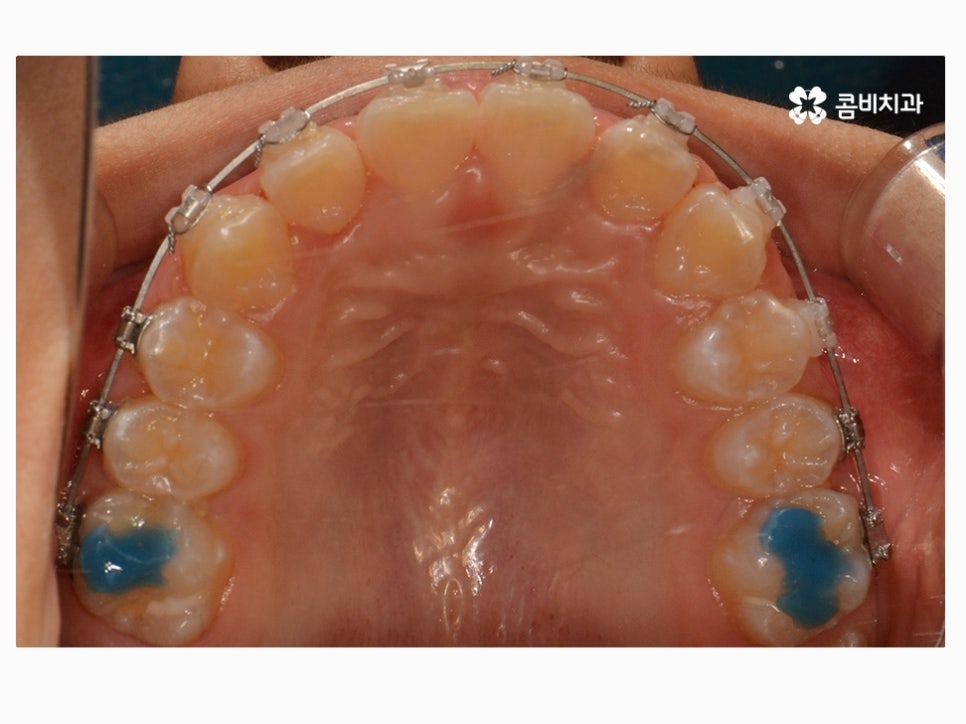

부정교합을 치료하는 방법은 나이대와 어떤 상태인지 진단에

따라서 달라질 수 있는데 위 케이스처럼 일반적인 치아교정으로

진행이 되는 경우도 있고 구외 교정 장치를 활용하는 경우 등 진단에 따라 다양할 수 있어요.

위 환자분께서 사용하신 장치는 클리피씨로 자가 결찰 장치이며

초기 통증이 줄어들고 관리가 용이하며 시술 기간을 단축시킬 수 있다는 장점이 있어요.